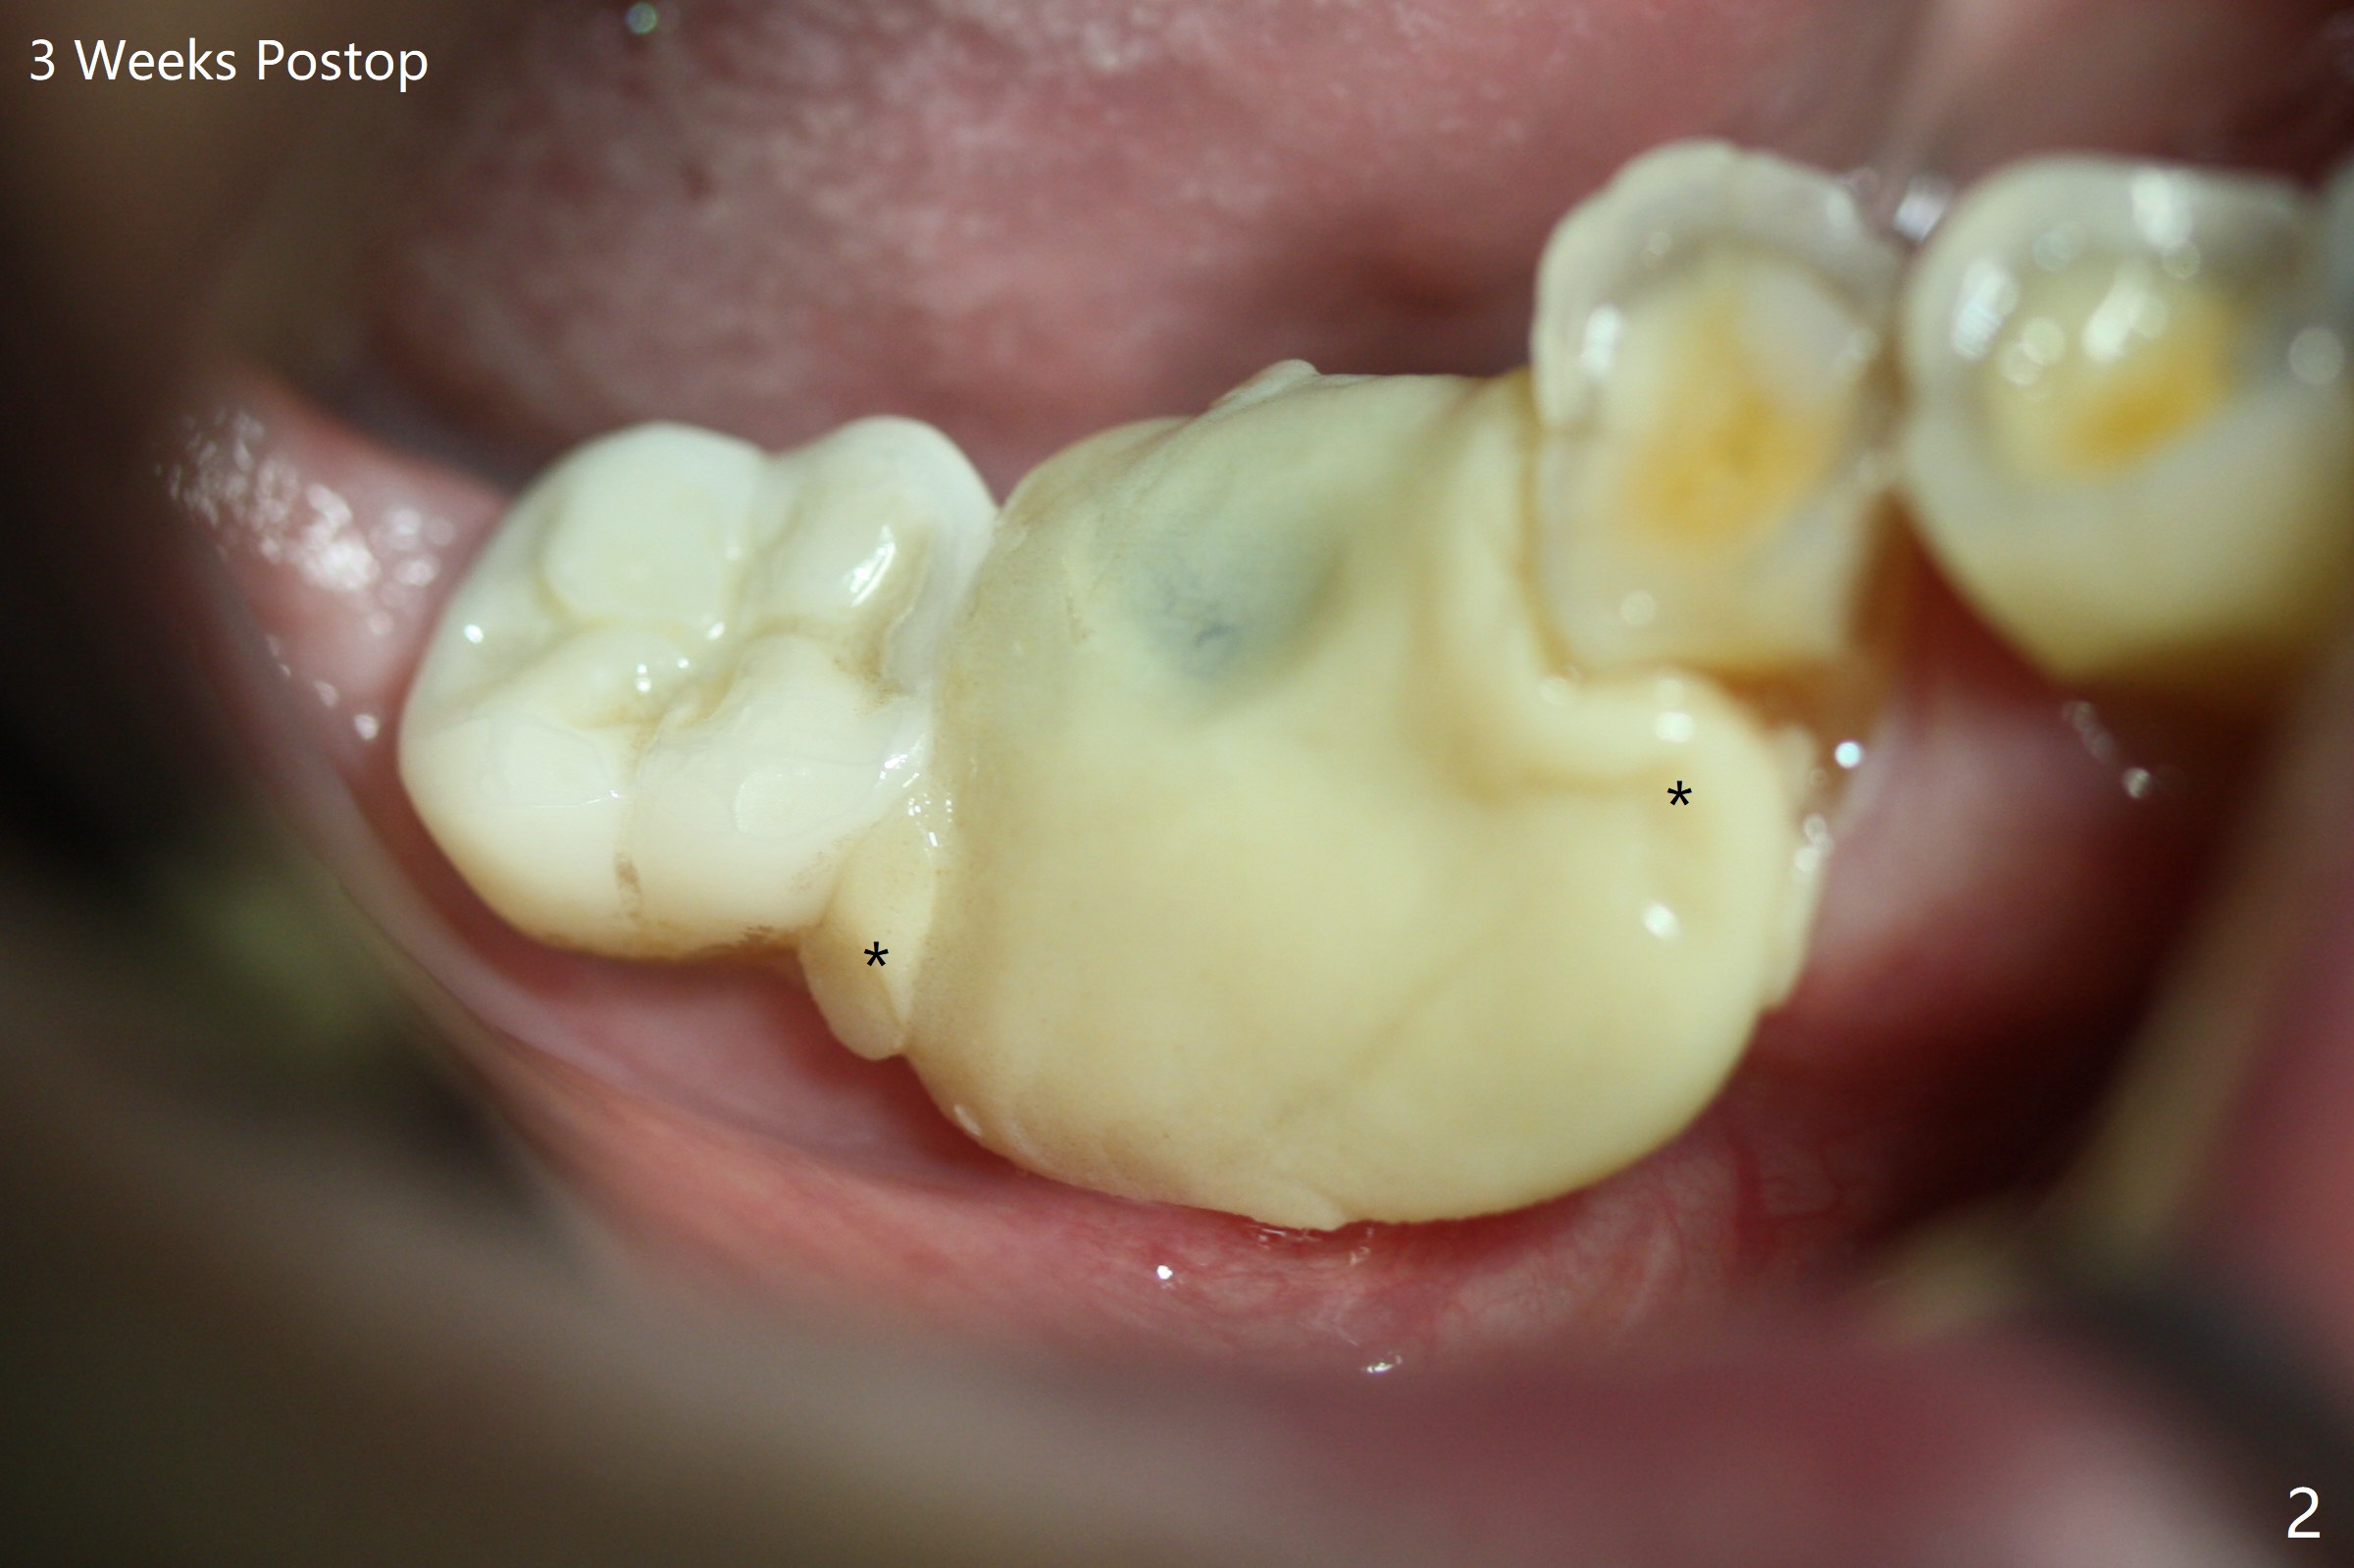

M

Vertical fracture of the mesial root of the tooth #30 after RCT is associated with bone loss (Fig.00 *). When the mesial portion of the mesial root (M', loose one) is exfoliated, the bone loss resolves (Fig.0). To reduce heat-induced bone necrosis at #19, osteotomy is conducted slowly with copious irrigation with cold saline. Bone density is felt while a 5x10 mm implant is being placed after using cortical tap to the 2nd line of the implant driver. The implant needs to be reverse torqued several times before reaching its final depth (Fig.1 (~50 Ncm)). Since the residual roots are superficially positioned, the immediate implant looks as a delayed one. Although the implant is placed mesial to the septum clinically, its position in X-ray seems to be normal. Because of severe wear and lack of vertical height, a 6.8x5 mm healing abutment is placed. Retention of bone graft (Fig.1 *) is maintained by spreading setting acrylic into the edentulous undercut areas (Fig.2 *). The so called "acrylic dressing" remains in place 3 weeks postop (Fig.8). When it is removed with the healing abutment, the wound heals (Fig.3). Note the limited vertical height. The bone graft placed in the distal socket appears to have been converted to the native bone 3.5 months postop (Fig.4). To reduce severe wear of the natural teeth, the occlusion of the new crown is not heavily decreased (Fig.5). It should be alright considering favorable crown/implant ratio (Fig.6). There is no bone loss 5 months post cementation, although the abutment screw is just retightened (Fig.7). In spite of poor trajectory associated with #18 (Fig.8) and 31 (Fig.7) Bicon implants, the abutments have not been dislodged. For the bruxer, the next implant at #19 with distal root fracture (Fig.8 ^) should be Bicon. The patient complains of food impaction nearly 1 year post cementation. The mesial and distal contacts of #30 crowns are light. When the abutment/crown is removed, there is implant well contamination (food debris). It appears that the previous abutment (5.7x4(2) mm, Fig.6,7) is incompletely seated. When a smaller abutment is placed and torqued at 30 Ncm, it is seated fully (Fig.9 (<: no gap)). New impression is taken. The distal gingival embrasure is larger than the mesial one because of the higher distal crest (Fig.6,7). If there is food impaction distal to the new crown, the distal crestal bone should be removed with lab closure of the embrasure.